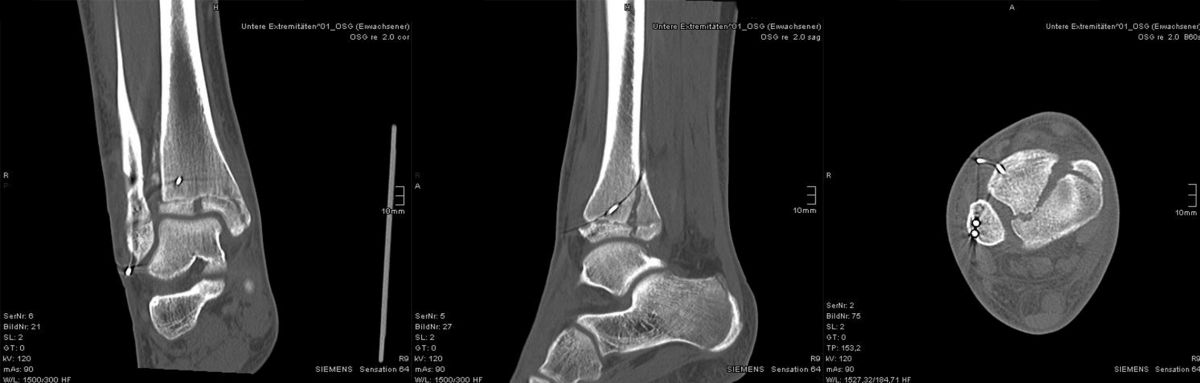

Computertomografie

Die Computertomografie liefert die höchste Auflösung für knöcherne Verletzungen und die Untersuchung dauert nur wenige Sekunden. Nachteilig ist die hohe Strahlenbelastung, die bei einem Vielfachen von konventionellen Röntgenbildern liegt. Bei komplexen Gelenksfrakturen hat die Computertomografie aber auch beim Kind ihre Berechtigung und erleichtert die Planung der Rekonstruktion.

MRT

Die Kernspintomographie hat ihre Stärke in der Darstellung von Weichteilverletzungen. Insbesondere Verletzungen der Wachstumsfuge, des Periosts und der Bänder lassen sich gut visualisieren. Nachteilig ist die Untersuchungsdauer von 20-30 Minuten. Bleibt das Kind während dieser Zeit nicht ruhig liegen, kommt es zu Bewegungsartefakten, welche die Beurteilbarkeit der Bilder beeinträchtigen.

Der teilweise komplexe Frakturverlauf bei Übergangsfrakturen lässt sich im CT zuverlässig darstellen 10. Der erfahrene Untersucher kann bereits mit Röntgenaufnahmen des Sprunggelenks in zwei Ebenen in Verbindung mit zwei 45° Schrägaufnahmen sehr umfassende Aussagen zum Frakturverlauf treffen (v. Laer 2013), die Präzision und Aussagekraft der Computertomografie ist aber zweifelsohne überlegen und wird von den meisten Behandlern bevorzugt 11, auch wenn sich zu diesem Thema in der Literatur eine teilweise sehr emotional geführte Diskussion findet. Einigkeit hinsichtlich der Indikation für ein Schnittbildverfahren besteht bei Triplane-Frakturen, wenn Zweifel darüber bestehen, inwieweit die metaphysäre Fraktur den tragenden Gelenkanteil tangiert 12.